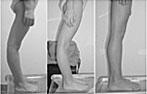

Behandlung / Korrektur von O-Beinen bei Kindern

9 Jahre alt nach 24 Monaten 10 Jahre alt nach 24 Monaten

Behandlung von O-Beinen und X-Beinen

O-Beine nach 36 Monaten X-Beine nach 36 Monaten

- Fehlformen der Beine korrigiert